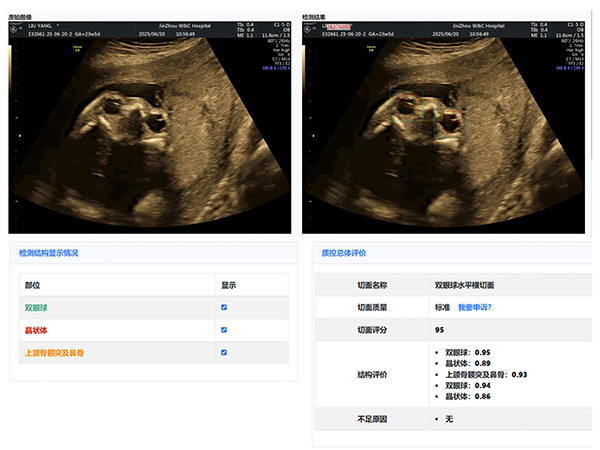

大赛汇聚了超声科全体医生,他们在产科超声领域各展所长。本次大赛引入了产前超声AI智慧云平台作为评分系统。

该平台利用先进的图像识别技术,对参赛的NT、I级、Ⅱ级、Ⅲ级产科超声图像进行精准分析与评分,确保了比赛的公正性与准确性,也体现了医院在医疗领域智能化、精准化的探索与进步。

经过激烈的角逐,年轻医生陈昱在NT产科超声图像评比中,凭借对NT精准的测量荣获第一名,展现出新生力量的专业风采;王斌医生在I级产科超声图像评比中,以精湛技术和对细节的精准把握摘得桂冠;刘芳医生的Ⅱ级产科超声图像作品,凭借清晰的图像质量和准确的诊断信息脱颖而出;Ⅲ级产科超声图像作品的评比竞争尤为激烈,李杭医生以微弱优势获得第一名。

大赛主持人超声科邵雪竹主任总结:“值此中国医师节举办图霸大赛,意义非凡。这不仅是技术的较量,更是我们交流学习的平台。通过活动,我们相互学习,共同提高,为患者提供更优质服务。AI智慧云平台的引入,标志着我院产科超声诊断迈向智能化、精准化。”

锦州市妇婴医院(妇幼保健院)作为锦州市权威产前诊断中心,肩负着对辖区内产前筛查机构(超声产前筛查切面完整率和超声产前筛查切面标准率等)的质控数据进行质量控制,超声科本次大赛初步尝试利用人工智能AI大数据技术开展质量控制与评价,取得了良好的效果。我们将以此为契机不断完善,促进全地区产前筛查服务的标准化、同质化。